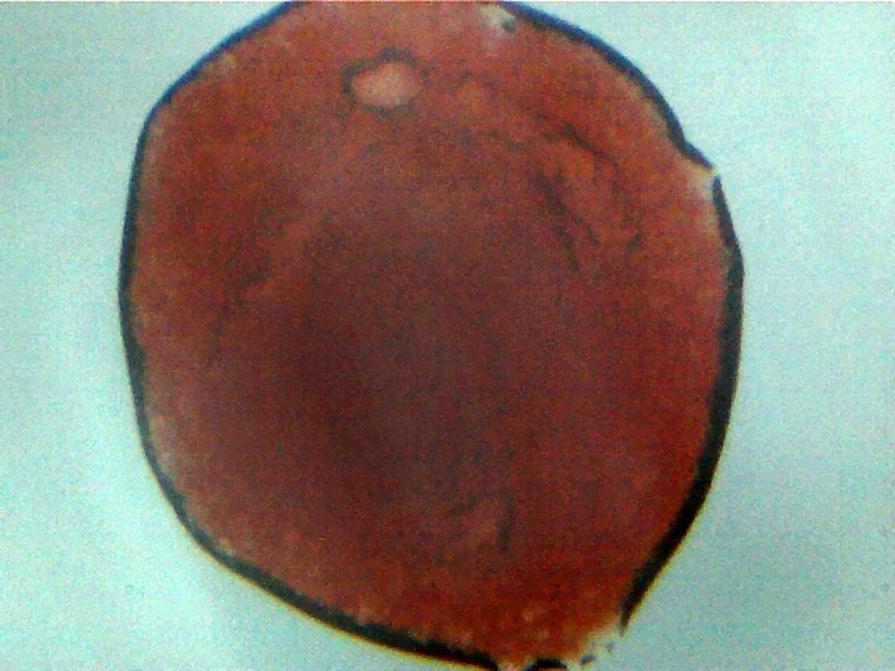

4 Digital Photography, Portrait, Nude, Human figure, Digital, 10x12.7cm Photographic paper Digital blood microscopic leukemia microscopic digital photography of my own Leukemia positive blood prior to treatment. Added 13 years ago 5 I Like I don't like 1 Comment 223 Visits Share Facebook Twitter Google + Has been liked by 5 Josef Rietzi Artist - Palma, Spain Geoff Dunlop Artist - Bristol, United Kingdom vincenzo lopardo Artist - Ascoli Piceno, Italy Anna Secondini Artist, Photographer - Urbino, Italy John Tran Artist - Tsukuba, Japan Comments 1 13 years ago Geoff Dunlop Artist A shockingly beautiful serious of images - rich with confusion and contradiction, like most of the best art. Say something You must login or Sign Up to write a comment Join